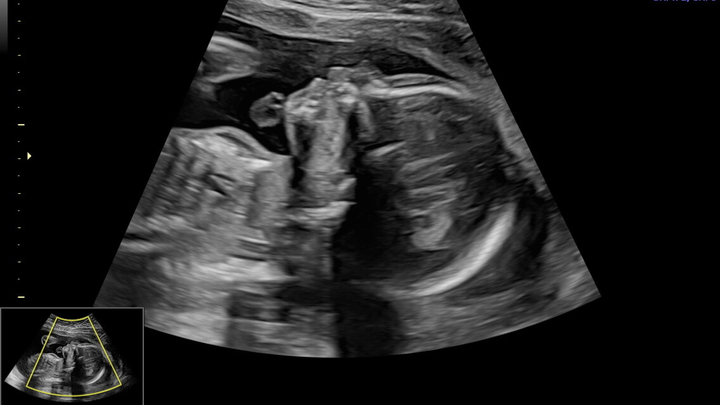

During this pregnancy, we learned that our baby has a severe congenital heart defect (Critical Aortic Stenosis.) Since that diagnosis, our lives have been turned upside down. We are facing constant appointments, repeated fetal echocardiograms, specialist consultations, and the reality that we must travel out of state for advanced fetal cardiac care.

There is a possibility of fetal heart intervention before birth, a procedure that carries significant risks — including the chance that it could be fatal to the baby. Every step forward comes with fear, uncertainty, and decisions no parent should have to make.